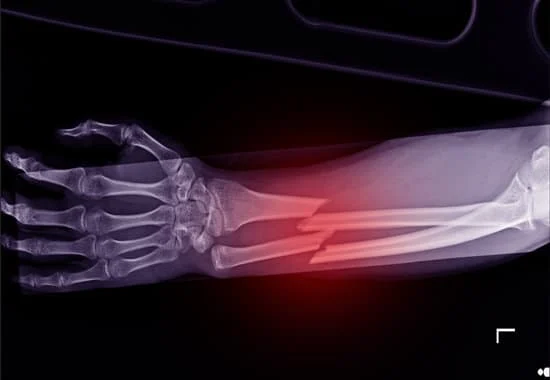

• All Trauma & Fracture Fixation (Nails, Plates, Non-union Repairs)

Quality and affordable healthcare has long been the essence in the field of medical sciences & treatment. Every patient expects an early diagnosis and a planned approach to treatment procedures with affordability and access to quality healthcare. Knee replacement, Hip replacement, Fracture treatment are being done by Dr.P.Sankaralingam at very affordable costs without compromising on quality.